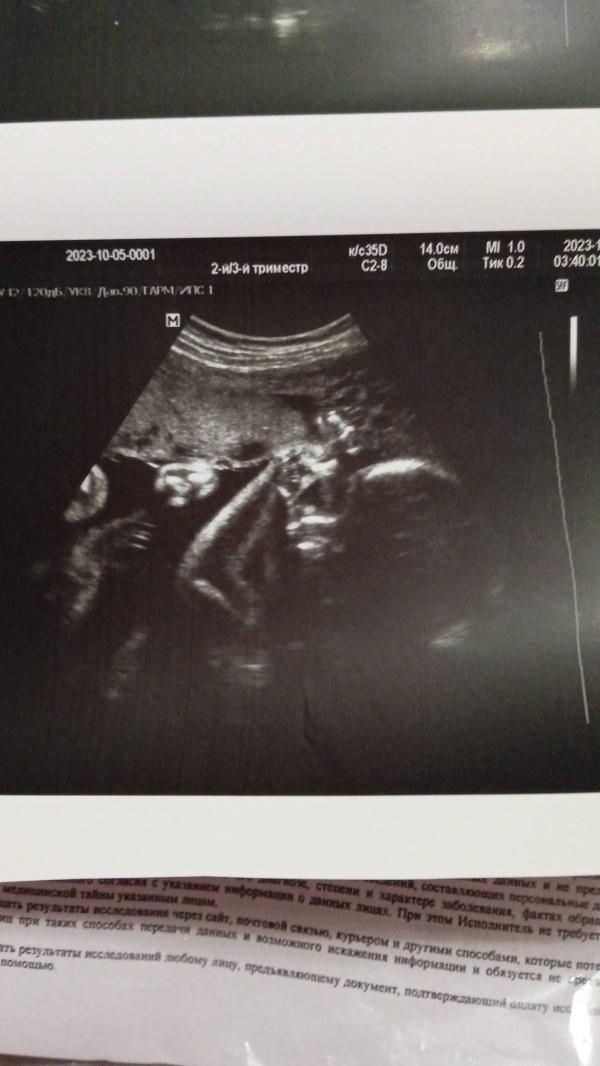

Сынок махал мне ручкой на УЗИ, которое быдо две недели назад 🙏интересно сколько он сейчас весит? Мамульки, а сколько весил ваш малыш на третьем скрининге? 🌷

32 недели -1700